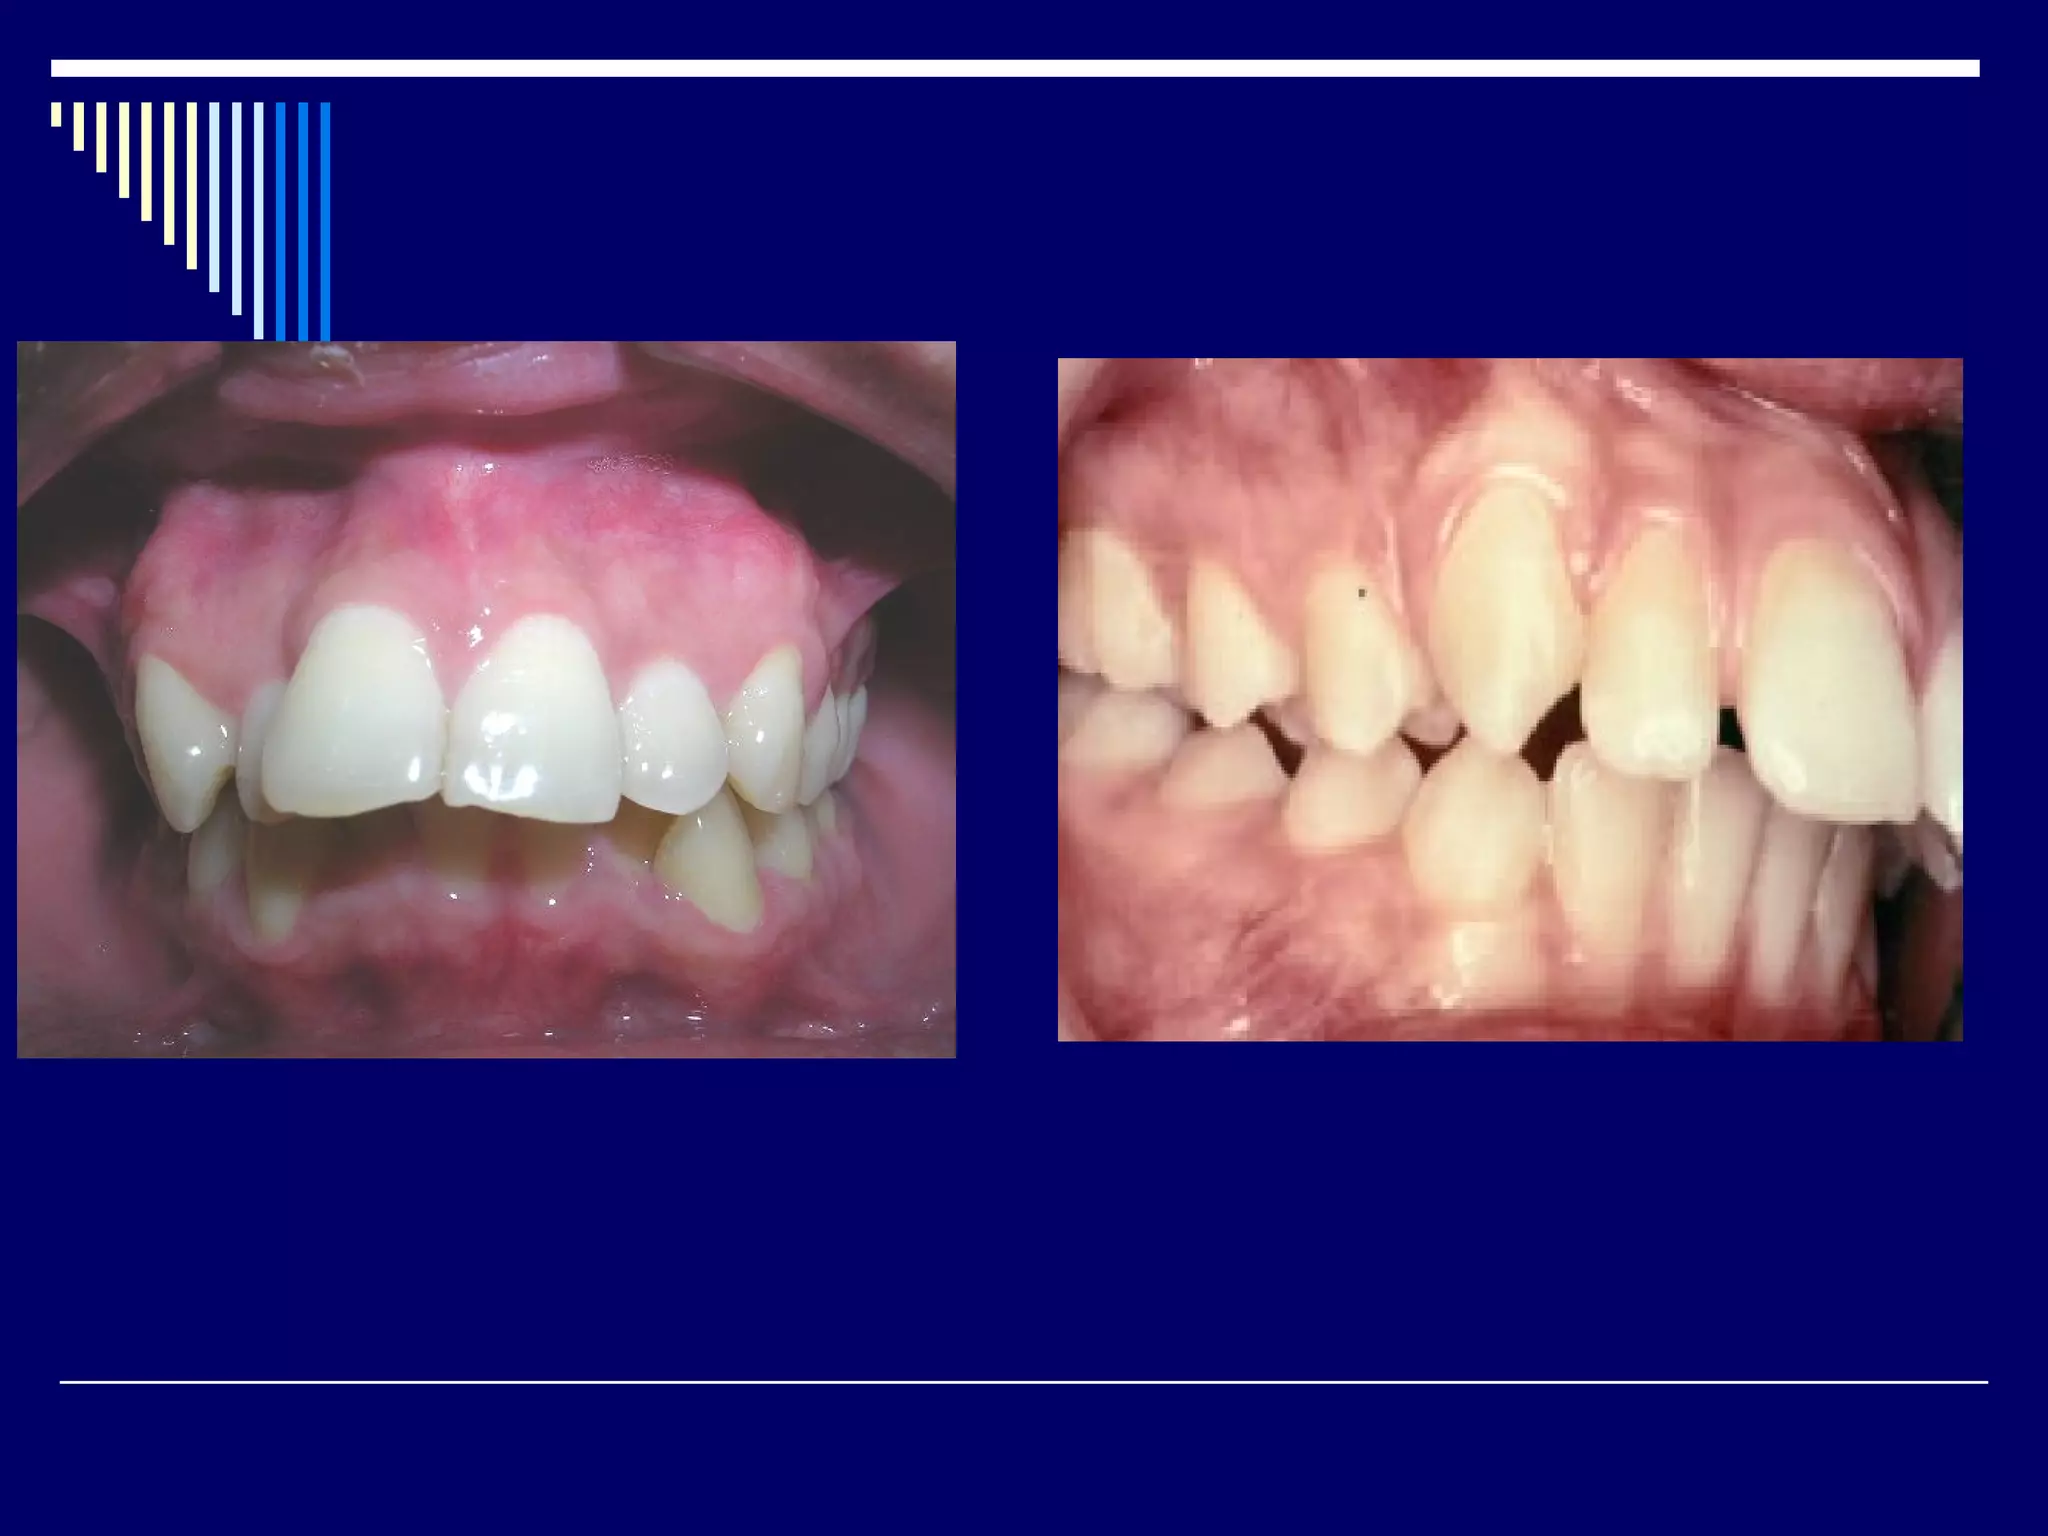

Class II division 2 malocclusion.

Molar relation is class II

The upper insisors are retroclined.

The laterals are overlapped the centrals

and the overbite is usually deep.

Class II division2 malocclusion. Molar relation is class II The upper insisors are retroclined. The laterals are overlapped the centrals and the overbite is usually deep.